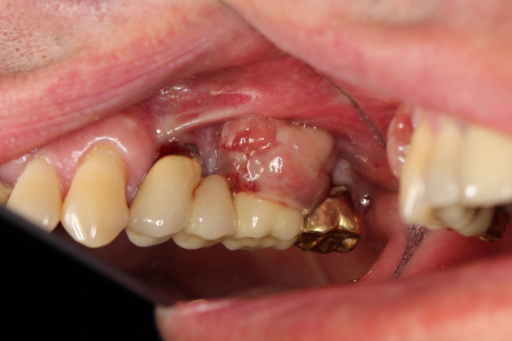

Descripción: Clinical examination revealed 7-mm probing depths, circumferentially around a mandibular implant, bleeding on probing, and the presence of exudate and gingival inflammatory edema

La periimplantitis se define como un proceso inflamatorio que afectan a los tejidos que rodean a un implante dental y que ocasiona una pérdida del soporte óseo en el que se ha integrado.

A term used to describe inflammation around a dental implant, usually the dental implant abutment.